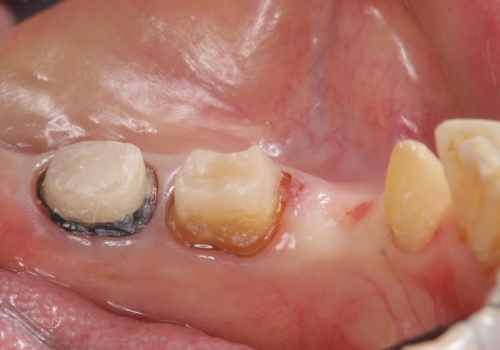

- 他院で右下小臼歯が保存不可能と言われ来院。当院の判断でも残念ながら抜歯となり、欠損部は抜歯後ブリッジにしました。右下奥2本が連結されていたため、そこは各々切り離した形で被せ物のやり替えも行っています。

抜歯後3か月ほど仮歯で生活していただき、欠損部の歯肉の状態が安定してからブリッジを入れています。